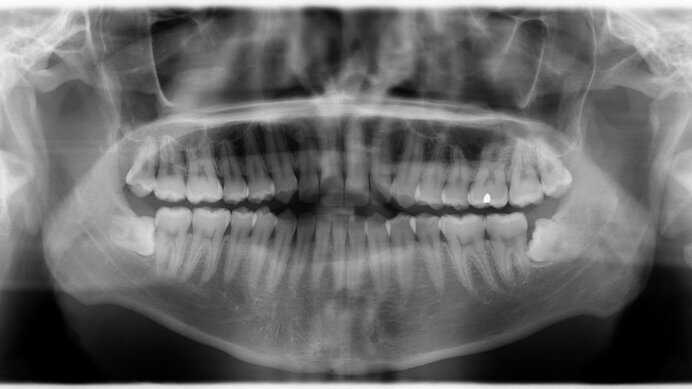

Ο θυρεοειδής αδένας στο λαιμό, εκτίθεται σε ακτινοβολία από τις πολλαπλές ενδοστοματικές ακτινογραφίες. Ο αδένας έχει ευαισθησία στην ιονίζουσα ακτινοβολία, ειδικά στα παιδιά. Οι ερευνητές σημειώνουν ότι η ενδοστοματική ακτινογραφία, μια πηγή χαμηλής ακτινοβολίας για διαγνωστικούς σκοπούς συχνά δεν θεωρείται δυνητικός κίνδυνος για το θυρεοειδή αδένα.

Οι ερευνητές μελέτησαν 313 ασθενείς στο Κουβέιτ που όλοι είχαν καρκίνο του θυρεοειδή. Στη χώρα αυτή η οδοντιατρική θεραπεία είναι δωρεάν. Σε σύγκριση με άλλες χώρες, η συχνότητα εμφάνισης του καρκίνου αυτού στο Κουβέιτ είναι υψηλή. Παρόλο που η μελέτη αυτή είναι μια από τις μεγαλύτερες που έχουν διεξαχθεί στο θέμα, οι ερευνητές σημειώνουν ότι τα αποτελέσματα πρέπει να αντιμετωπιστούν με προσοχή, καθώς τα δεδομένα συλλέχθηκαν από τους ίδιους τους συμμετέχοντες. Οι ερευνητές πιστεύουν ότι η μελέτη τους παρέχει ισχυρά πειστήρια ώστε να ενθαρρυνθεί περαιτέρω η έρευνα σε χώρες και εγκαταστάσεις όπου τα αρχεία ιστορικού των ενδοστοματικών ακτινογραφιών είναι διαθέσιμα και όπου η δόση της ακτινοβολίας μπορεί να εκτιμηθεί με βεβαιότητα.